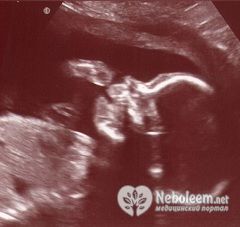

Актуальными для данного срока беременности остаются анализы крови и мочи. Врач направляет на ультразвуковое обследование тех беременных, которые не прошли его в 20 – 22 недели. УЗИ в 23 недели беременности позволяет узнать и пол будущего младенца.